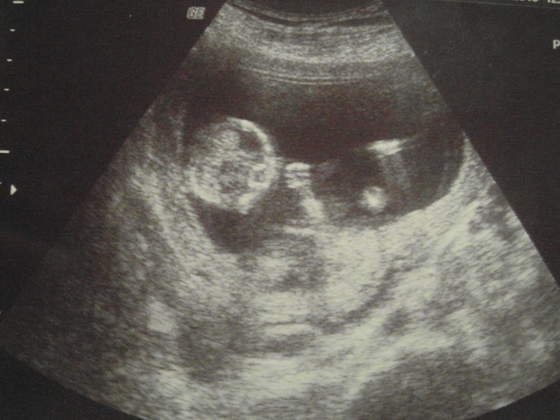

08.06/04.10/09.13

Ja też dzisiaj u ginki byłam. Mam się oszczędzać, taaa. Oczywiście pessar mnie nie ominie, liczyłam się z tym, ale myślałam, że jeszcze nie będzie na ten temat

Kolejna wizyta 14.03.